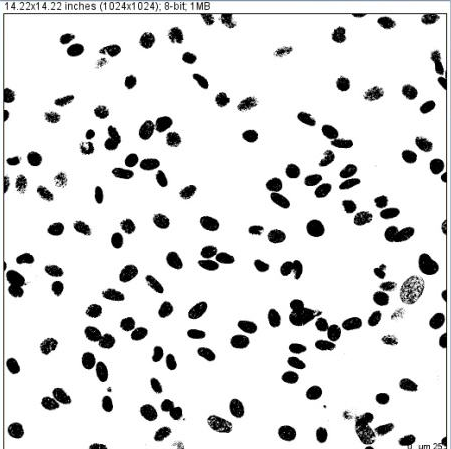

此外,基于物体的边缘呈现灰度的不连续性的原理还可以进行图像分割,常用于生物医学图像的分析,用于测量人体器官、组织或病灶的体积,用于医学图像的3D重建,例如两个彗星细胞粘连的情况,提出一种基于区域灰度值的路径探测方法.对粘连细胞进行分割,便于可视化,可取得较理想的分割效果。另外,也可以用灰度值实现显微图像的细胞计数判读。

灰度图像拍摄与判读目前多数是用独立的两个软件进行拍摄与图像处理分析,将图像拍摄成特定的格式后通过分析软件转换深度实现灰度分析,软件来回切换给使用者带来很大的不便。广州明美可定制兼容8、12位深度拍摄和灰度识别的软件,在同一个软件上实现灰度图像拍摄及灰度识别分析,填补了市场空白,便捷性与实用性大大提升。

下图为中空毛细管在明美显微镜下的12位图①灰度分析图片,以熔融石英毛细管为Immunoassay载体材料, 通过化学发光成像和灰度分析, 建立了血清特定物质的定量Immunoassay检测方法。基于毛细管为载体的灰度分析immunodetection方法 适用化学发光Immunoassay, 具有普适性和较好的临床检验应用前景,为体外诊断的普及及准确性提供强有力的支撑。